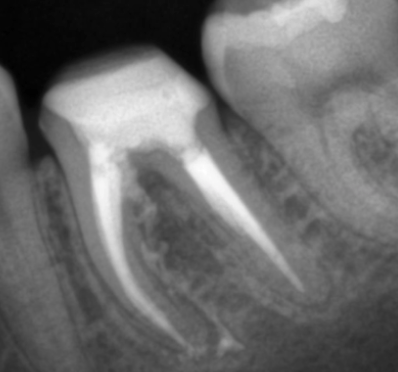

Extinderea tratamentului endodontic la nivelul întregii anatomii este mai sigură în cazul folosirii microscopului operator. În această situație, acestui molar inferior i-au fost tratate 3 canale, așa cum este forma anatomică (Fig. 4.12.1). Doar că în această situație sistemul endodontic prezenta 6 canale, toate instrumentate și obturate cu ocazia retratamentului. (Fig. 4.12.2, Fig. 4.12.3)

În acest caz, pacientul s-a prezentat după un abces acut în antecedente (durere puternică și spontană, cu caracter pulsatil) care a fost tratat cu antibiotice. La analiza imagisticii 3D remarcăm că există o comunicare între materialul din interiorul dintelui și spațiul dintre cele două rădăcini. Se mai evidențiază și material extrudat în acest spațiu, precum și pierdere osoasă. Deducem că este vorba de pierdere osoasă în furcație în urma cimentării unui pivot turnat. Acest pivot a fost cimentat într-un spațiu artificial creat în afara rădăcinii, această acțiune fiind un accident al tratamentului inițial (Fig. 4.12.4). Prima măsură este de a asigura izolarea cu diga dentară. Dintele prezintă o coroană artificială ce trebuie îndepărtată, diga ferește pacientul de contactul cu pulberile rezultate în urma tăierii coroanei (Fig. 4.12.5).

Un astfel de tratament reușește dacă osul se regenerează iar acest proces este observabil după câteva luni. În acest caz, la radiografia de control de la 6 luni putem să remarcăm că osul este regenerat, dintele asimptomatic și funcțional (Fig. 4.12.12).